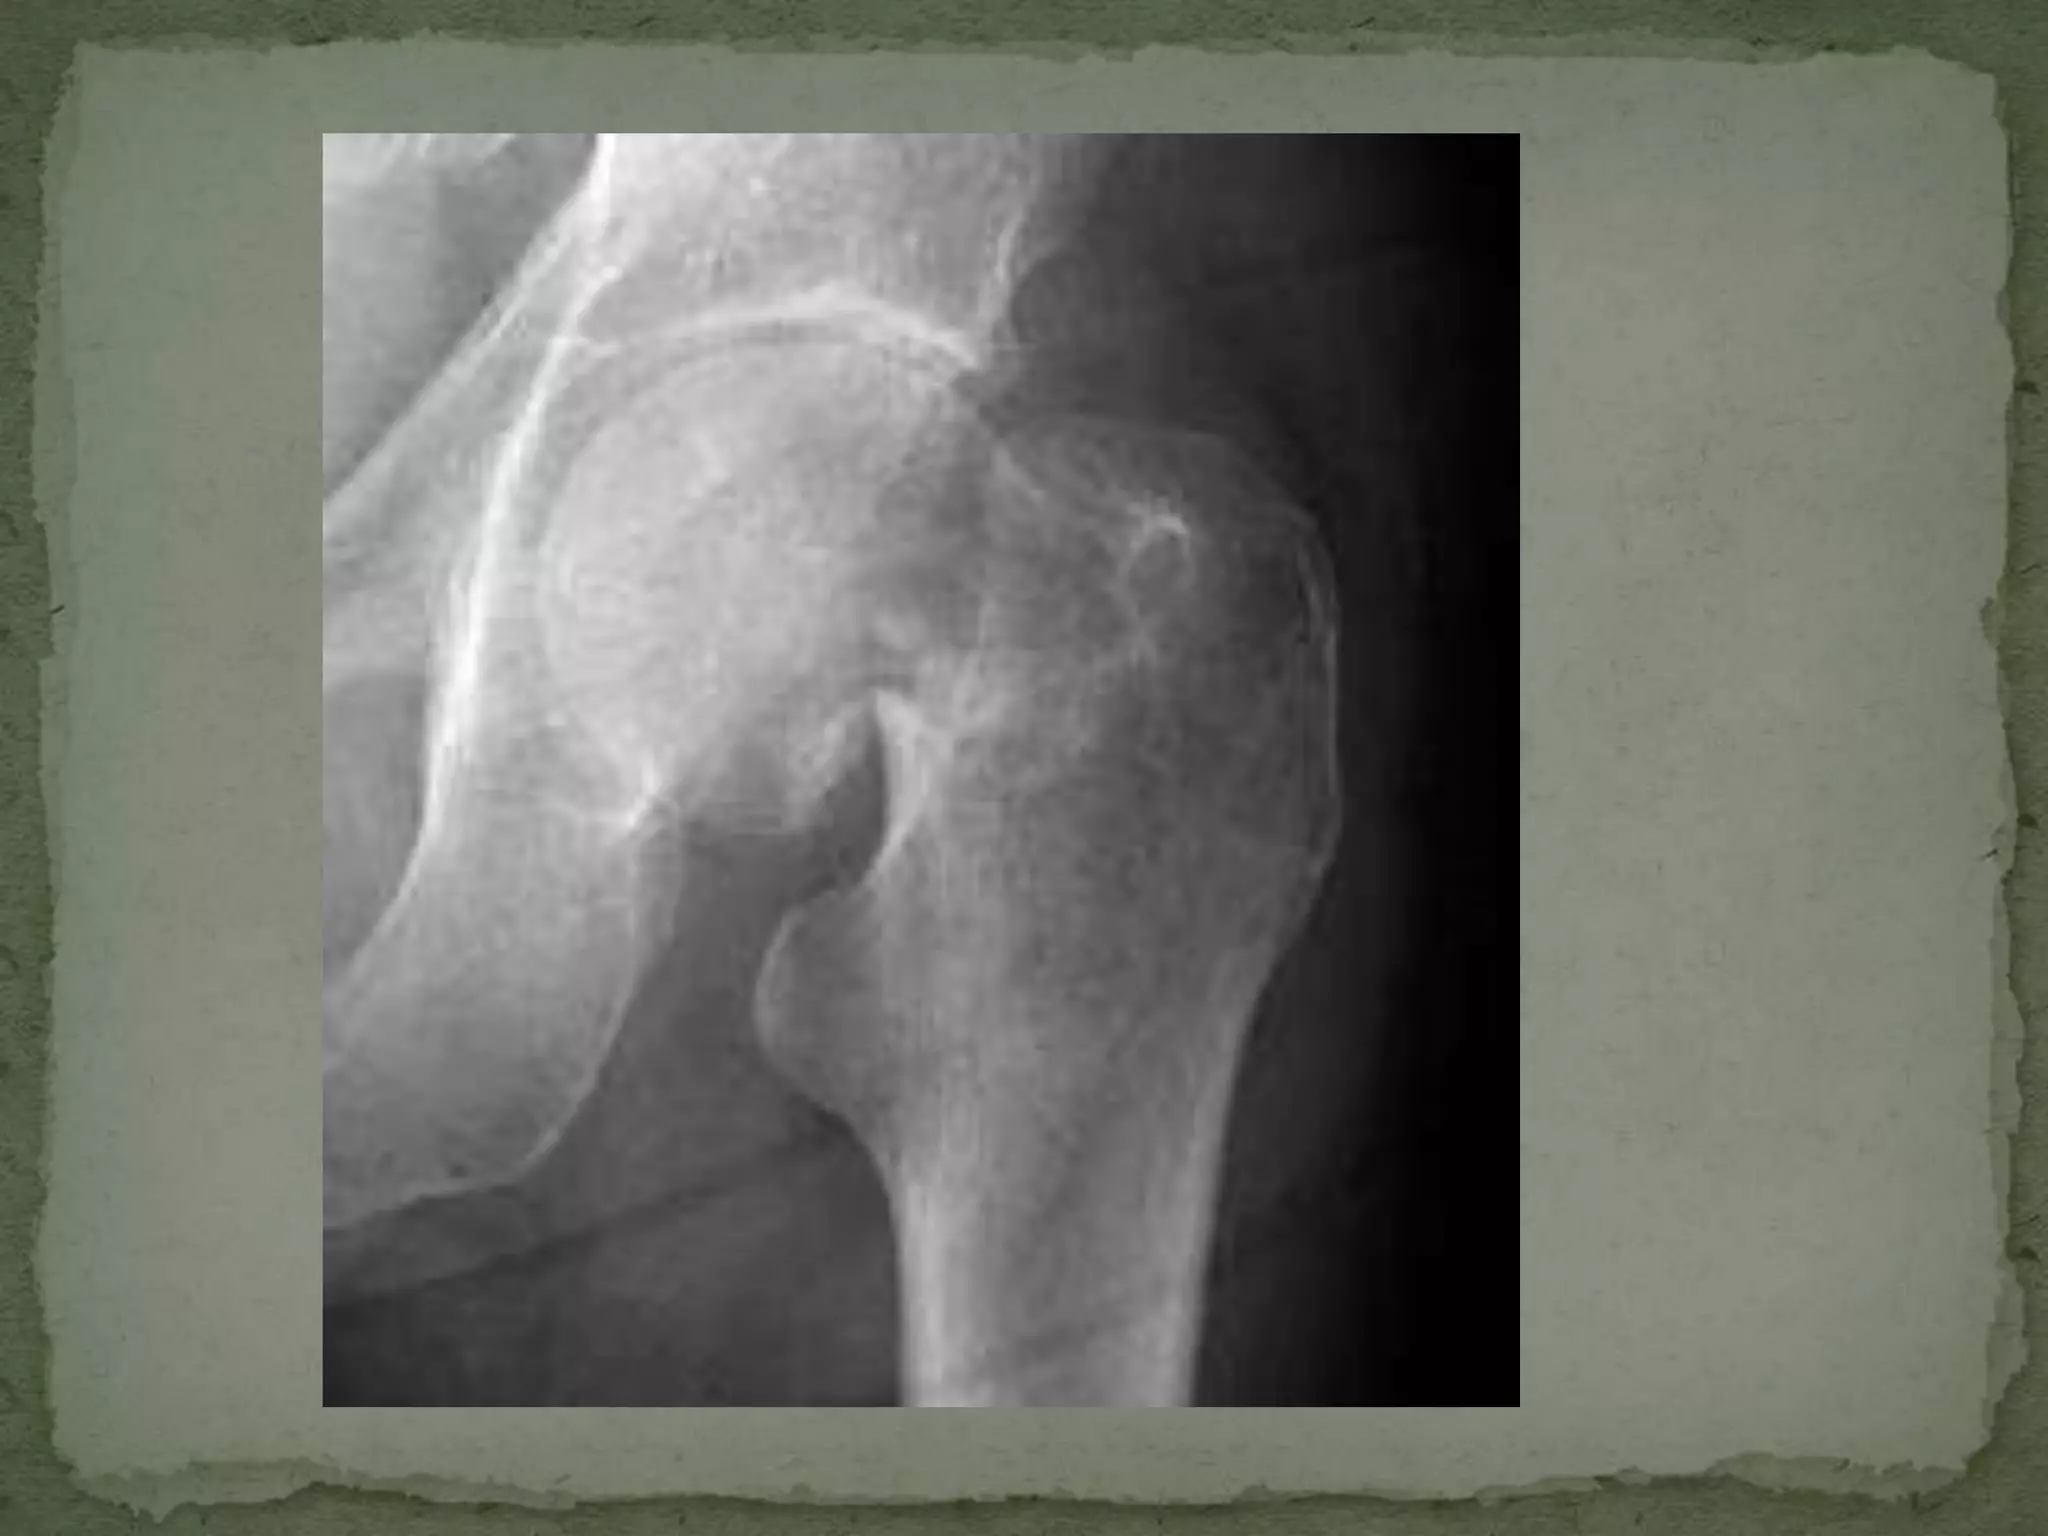

A 78-year-old woman fell at home and presented with left hip pain. On examination, her left hip was tender to touch and externally rotated and shortened, consistent with a femoral neck fracture. She will need pain control, evaluation for potential medical causes of the fall, orthopedic consultation, and operative management given the risks of increased mortality associated with delays in surgical repair for hip fractures in elderly patients.